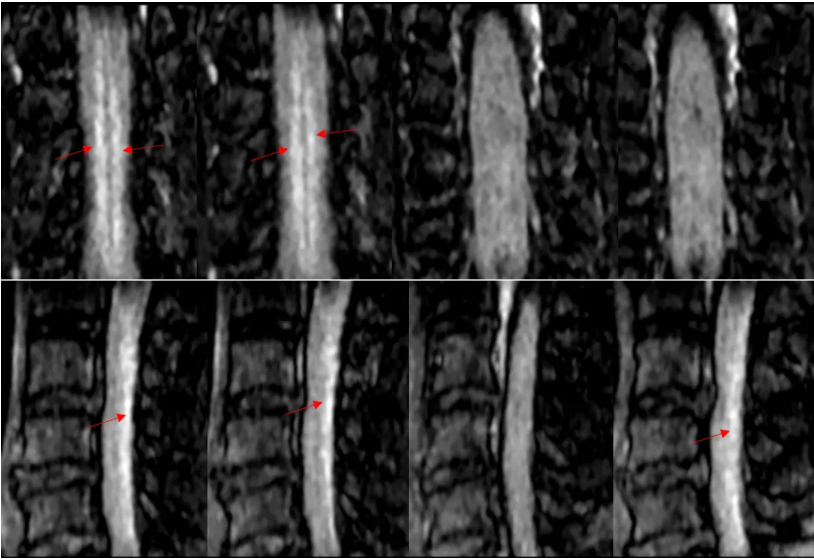

重建效果图:

五、综合诊断 脊髓亚急性联合变性(SCD) v由于维生素B12的摄入、吸收、结合、转运或代谢障碍导致体内含量不足而引起的中枢和周围神经系统变性的疾病。 v主要累及脊髓后索、侧索及周围神经,影像表现为倒置的“V”。 追问病史,该患者有长期大量饮酒史,胃功能受损